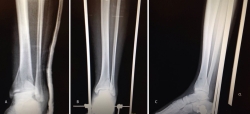

Figura 17. Caso 3: fractura tipo C. Radiografías sin tracción y con tracción comprobando la reducción.

Figura 18. La tomografía computarizada muestra los fragmentos principales de la fractura, estando desplazado el Tillaux que se reduce con la tracción.